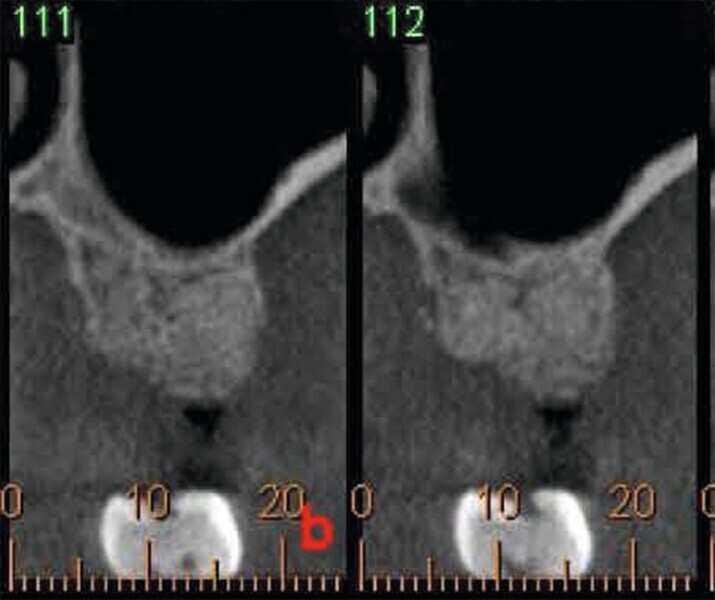

Fig. 46 : Deuxième molaire supérieure compromise (fissure et complication endodontique).

Fig. 47 : Deuxième molaire supérieure compromise (fissure et complication endodontique).

Fig. 48 : Deuxième molaire supérieure compromise (fissure et complication endodontique).

Le diagnostic a établi une atteinte de la furcation de la deuxième molaire supérieure, accompagnée d’un mauvais pronostic en raison d’une fissure inter-radiculaire. La dent a été extraite délicatement, de façon à conserver le septum inter-radiculaire dans le site où il était prévu de poser l’implant. La technique d’ostéodensification a été effectuée à l’aide de fraises Densah (Versah) et a permis d’obtenir une excellente stabilité de l’implant au niveau tissulaire. Une allo-greffe constituée d’un substitut osseux et un ciment au sulfate de calcium biphasique ont été utilisés pour préserver l’alvéole. Après huit semaines, nous pouvions constater et apprécier l’intégration parfaitement réussie de l’implant en céramique dans le tissu péri-implantaire (Figs. 46–56).